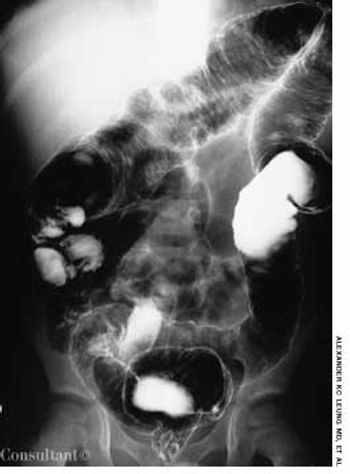

A 6-year-old boy presented with bloody diarrhea; fatigue; decreased appetite; weight loss; and occasional, mild abdominal pain for the past 2 months. The child had 6 to 8 bowel movements daily, 1 or 2 of which occurred at night.

A 6-year-old boy is brought for evaluation of bloody diarrhea, fatigue, decreased appetite, weight loss, and occasional, mild abdominal pain of 2 months' duration. The child had 6 to 8 bowel movements daily, 1 or 2 of which occurred at night.